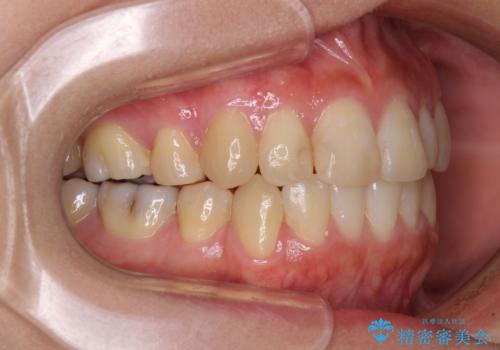

治療期間はかかりましたが、正中も合い、綺麗な仕上がりとなりました。